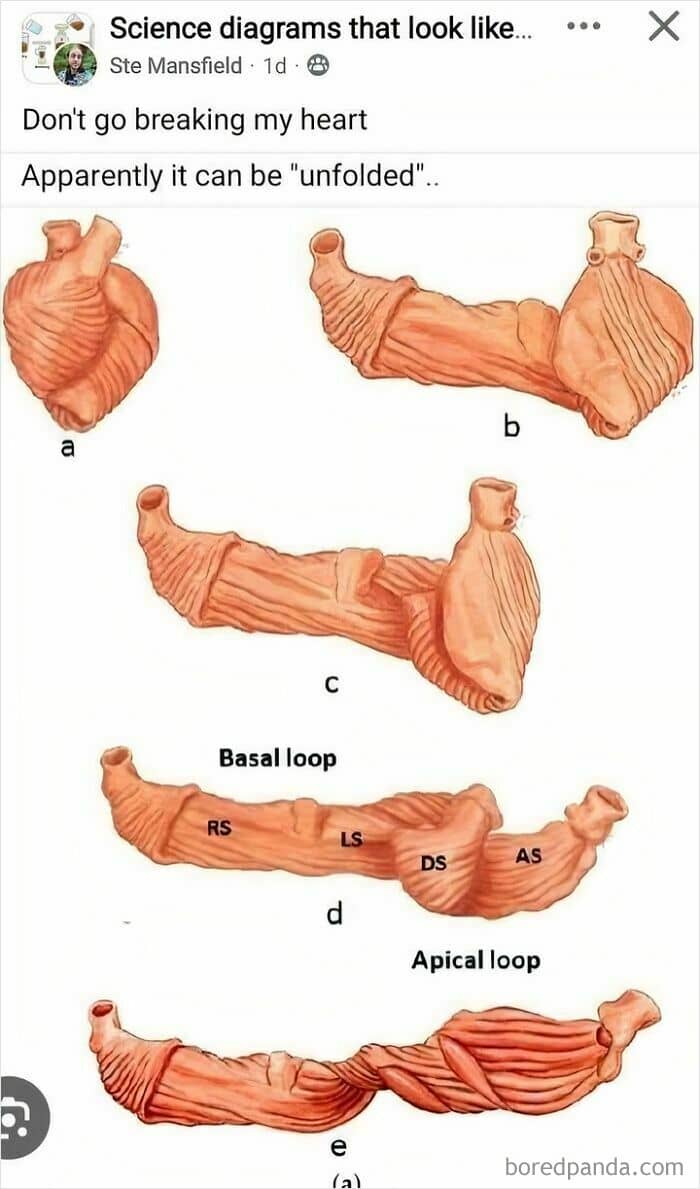

#38 Thanks, I Hate Unfolding A Heart